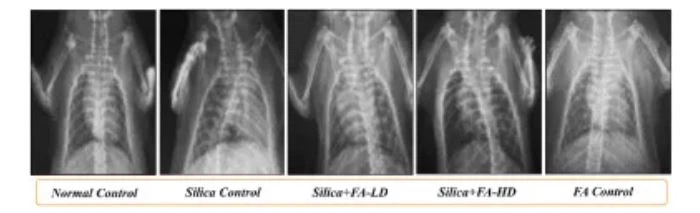

결과는 페룰산이 비정상 폐 형태와 실리카로 인한 폐 지수 증가를 크게 개선하고 BALF(총 세포, 림프구, 대식세포, 호중구 포함)에서 염증 세포의 이동을 개선할 수 있음을 보여주었습니다. 세포 및 백혈구), 폐 병리학적 병변 및 ECM 침전을 완화하는 동시에 실리카에 의해 유도된 PF 모델에서 조직 산화 스트레스 및 아질산염 수치 상승을 완화합니다. 폐의 X-선 관찰은 실리카 유도 후 14일에 미만성 폐포 경화를 나타냈다. 이러한 변화는 PF의 초기 단계에서 일반적이며 ferulic acid는 실리카로 인한 병리학 적 손상을 부분적으로 되돌릴 수 있습니다. 염증은 PF의 발병기전에 중요한 역할을 합니다. 연구자들은 실리카 그룹에서 TNF-α, IL-6 및 IL-1β의 수준이 크게 증가했으며 페룰산이 이러한 전염증 인자의 발현을 크게 감소시킬 수 있음을 발견했습니다. . 실리카는 폐 조직의 총 콜라겐 함량 증가를 유도하고 TGF-β 신호 전달 경로를 상향 조절하는 반면, 페룰산은 섬유 생성 경로와 밀접하게 관련된 신호 전달 경로 단백질(콜라겐-I, CTGF, 슬러그 및 p 포함)을 하향 조절합니다. -smad2/3) 발현은 실리카로 인한 PF 병변을 개선합니다. 마지막으로, 연구자들은 또한 페룰산이 이산화규소로 유도된 상피에서 중간엽으로의 전이(EMT) 과정을 개선하고 폐 조직 병변을 보호할 수 있음을 입증했습니다. 연구자들은 또한 단일 위관 영양 실험에 사용된 고용량 페룰린산이 잠재적인 폐 독성을 유발하지 않음을 증명하여 이산화규소로 인한 폐 손상에 대한 페룰산의 보호 효과를 입증했습니다.

폐의 대표적인 X선 사진